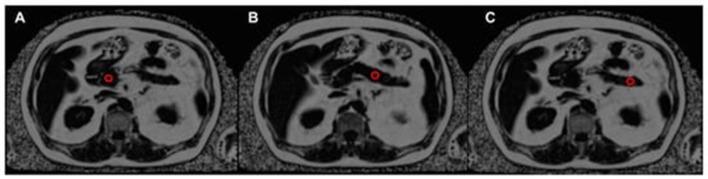

Fatty infiltration of the pancreas (FIP) has been recognized for nearly a century, yet many aspects of this condition remain unclear. Regular literature reviews on the diagnosis, consequences, and management of FIP are crucial. This review article highlights the various disorders for which FIP has been established as a risk factor, including type 2 diabetes mellitus (T2DM), pancreatitis, pancreatic fistula (PF), metabolic syndrome (MS), polycystic ovary syndrome (PCOS), and pancreatic duct adenocarcinoma (PDAC), as well as the new investigation tools. Given the interdisciplinary nature of FIP research, a broad range of healthcare specialists are involved. This review article covers key aspects of FIP, including nomenclature and definition of pancreatic fat infiltration, history and epidemiology, etiology and pathophysiology, clinical presentation and diagnosis, clinical consequences, and treatment. This review is presented in a detailed narrative format for accessibility to clinicians and medical students.

胰腺脂肪浸润(FIP)已被认识近一个世纪,但这种病症的许多方面仍不清楚。定期对FIP的诊断、后果及管理进行文献综述至关重要。这篇综述文章强调了已确定FIP为风险因素的各种疾病,包括2型糖尿病(T2DM)、胰腺炎、胰瘘(PF)、代谢综合征(MS)、多囊卵巢综合征(PCOS)和胰腺导管腺癌(PDAC),以及新的研究工具。鉴于FIP研究的跨学科性质,涉及广泛的医疗保健专家。这篇综述文章涵盖了FIP的关键方面,包括胰腺脂肪浸润的命名和定义、历史和流行病学、病因和病理生理学、临床表现和诊断、临床后果及治疗。本综述以详细的叙述形式呈现,以便临床医生和医学生查阅。